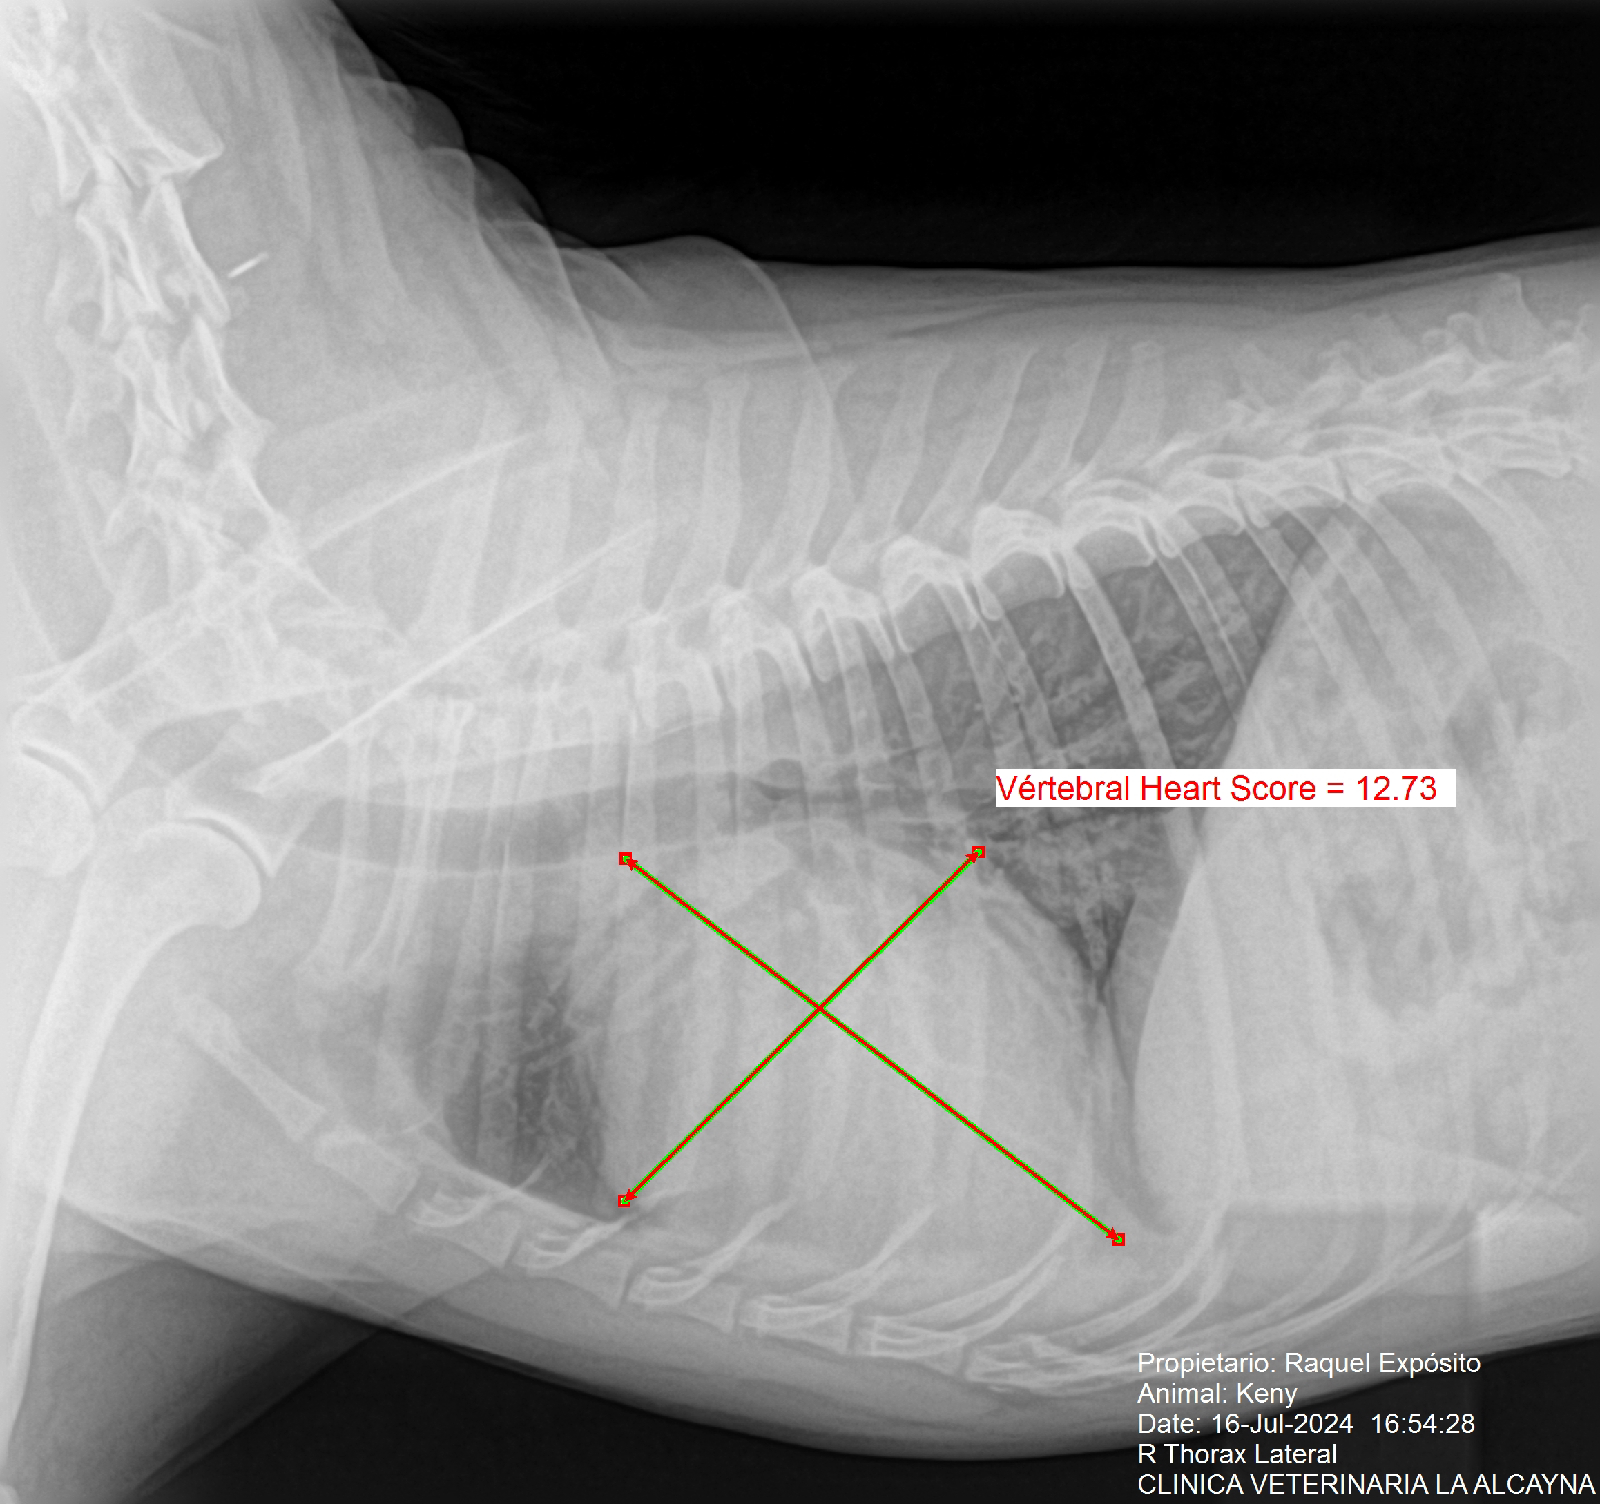

En cuanto se recuperó, llamé al veterinario y a primera hora de esta tarde le han hecho varias pruebas: el examen neurológico y la tensión, estaban perfectos, pero en la auscultación, han notado problemas, que se han confirmado con Rx.

El corazón está agrandado, le comprime la tráquea y la caja torácica, por lo que dificulta el bombeo de sangre, esa posible fatiga en el transporte de oxígeno, le ha causado el síncope. 😟

El rango normal en la escala cardíaca vertebral, está entre: 9,2 y 10,3